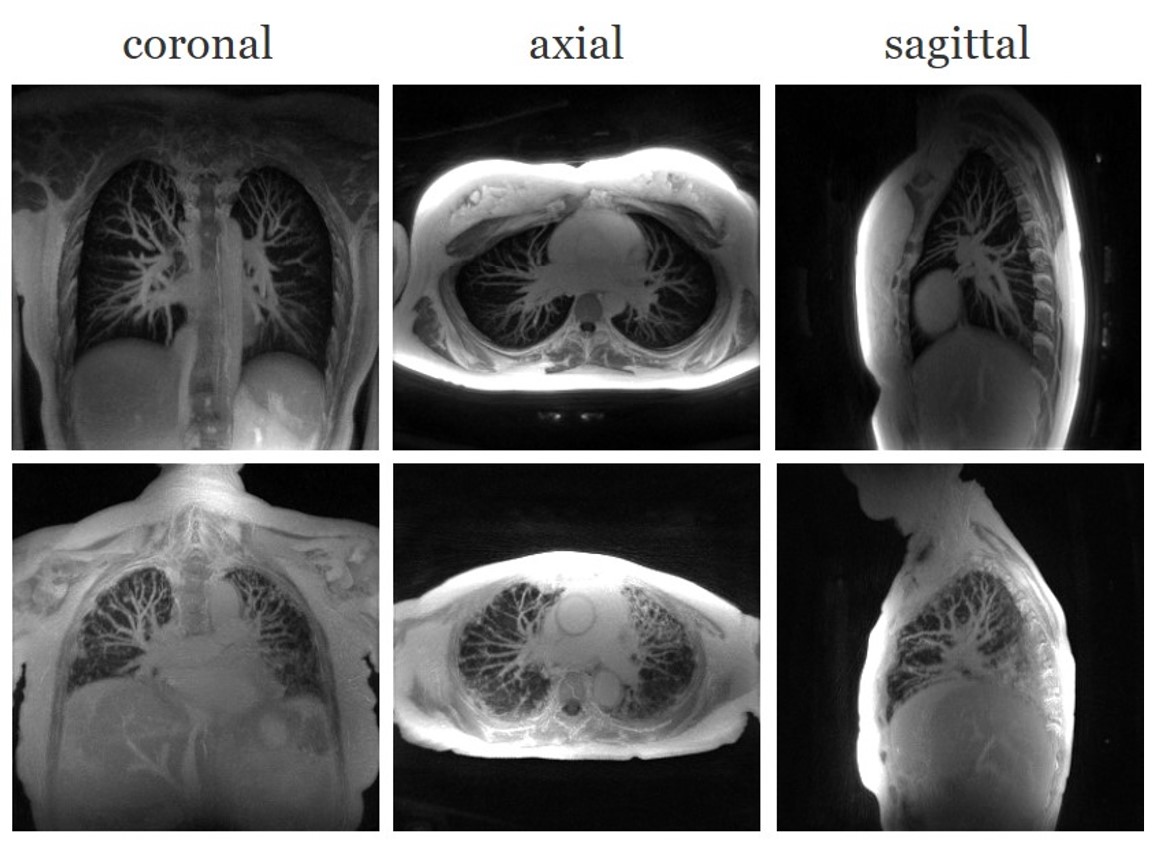

4.5 Maximum intensity projections of the reconstructions

In this section, we show some results that we obtained from the proposed MoCo-SToRM reconstructions. In Fig. 9, we show the reconstructions obtained from two post-contrast datasets, one from a healthy subject and anther from a diseased subject. Maximum intensity projection (MIP) [32] is used to generate the results. MIP is known to have the benefit that the vascular structures can be clearly seen as tubular and branching structures in MIP images [33]. By showing the three views for the reconstruction using MIP, the lung structure and vascular structures for each subject can be seen in a direct way, which can be readily used by doctors in clinics. For each sub-figure in Fig. 9, 20 slices are used for MIP images.

Refer to caption

Figure 9: Showcase of the proposed scheme on the post-contrast data from both the healthy subject and the fibrotic subject. Maximum intensity projection of three views are shown for each dataset.